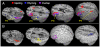

Previous studies have shown that developmental changes in the structure and function of prefrontal regions can continue throughout childhood and adolescence. Our recent results suggested a role for the left inferior frontal cortex in modulating task-dependent shifts in effective connectivity when adults focus on orthographic versus phonological aspects of presented words. Specifically, the top-down influence of the inferior frontal cortex determined whether incoming word-form information from the fusiform gyrus would have a greater impact on the parietal areas involved in orthographic processing or temporal areas involved in phonological processing (Bitan, T., Booth, J.R., Choy, J., Burman, D.D., Gitelman, D.R. and Mesulam, M.-M., 2005. Shifts of Effective Connectivity within a Language Network during Rhyming and Spelling. J. Neurosci. 25, 5397-5403.). In the current study, we find that children displayed an identical pattern of task-dependent functional activations within this network. In comparison to adults, however, children had significantly weaker top-down modulatory influences emanating from the inferior frontal area. Adult language processing may thus involve greater top-down cognitive control compared to children, resulting in less interference from task-irrelevant information.